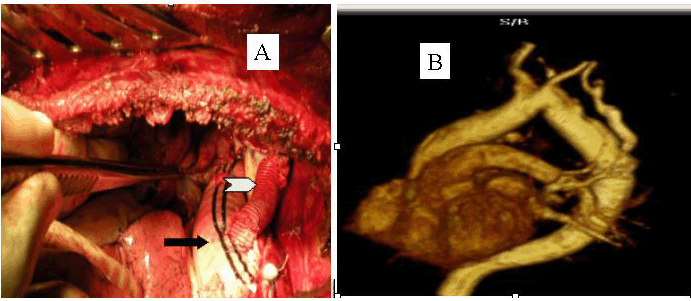

Figure 1: A) Digital subtraction angiography showing pre (white arrow) and post subclavian coarctation of aorta (black arrow head) and aberrant right subclavian artery (black arrow) and distal aortic arch aneurysm, B) per-operative photo showing large aneurismal sac (white arrow) extending upto the apex of the left thoracic cavity.

Figure 2: Intra-operative photograph showing aortic prosthesis (black arrow) with a side limb (white arrow) to the left subclavian artery, B) Magnetic resonance angiography six months after surgery showing patent grafts.